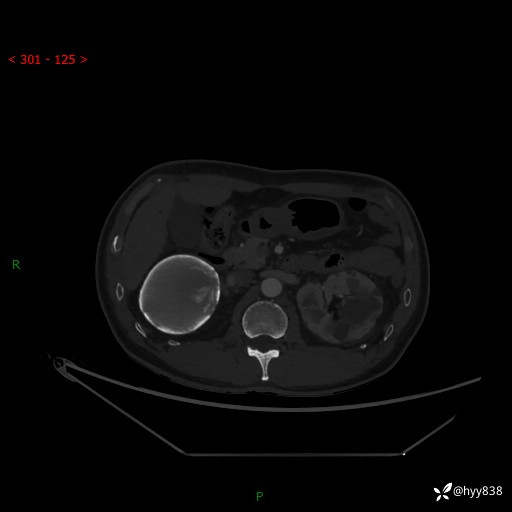

性别:男

年龄:50岁

简要病史:夜尿增多半月,发现肾功能异常1天,超声发现腹膜后占位

腹部CT平扫+增强